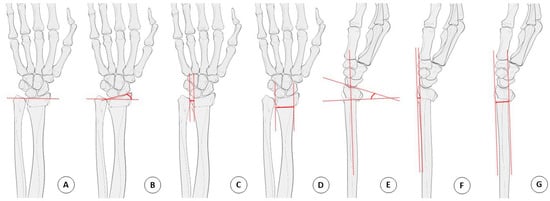

A standard 4 view x-ray of the injured wrist, and AP and lateral views of the uninjured side were obtained for all patients. Measurement of the DRUJ gap distance was performed on both sides in order to better evaluate widening of the DRUJ. The DRUJ distance was defined as the maximum distance between either the volar or dorsal cortical rim of the sigmoid notch of the radius and the ulnar head. The radial translation ratio was calculated as the fraction of the DRUJ gap distance relative to the radioulnar width of the proximal fracture fragment. On the lateral X-ray, the sagittal translation was defined as the distance between the volar cortex of the radius shaft and the volar cortical margin of the distal fracture fragment. The sagittal translation ratio was calculated as the fraction of the sagittal translation to the AP width of the proximal fracture fragment [2,8].

The radial length was defined as the distance between two lines drawn perpendicular to the long axis of the radius on the AP projection from the apex of the radial styloid and the level of the ulnar aspect of the articular surface. The radial length was measured on the uninjured wrist, and the radial length gap between both sides of the wrist was obtained for the evaluation of the pure radial shortening distance (Figure 2).

Figure 2. Radiologic parameter measurement technique. (A) Radial length. (B) Radial inclination. (C) DRUJ distance. (D) Fracture site width. (E) Dorsal angulation. (F) Sagittal translation. (G) Anteroposterior width. Radial translation ratio = C/D, Sagittal translation ratio = F/G. DRUJ, distal radioulnar joint.